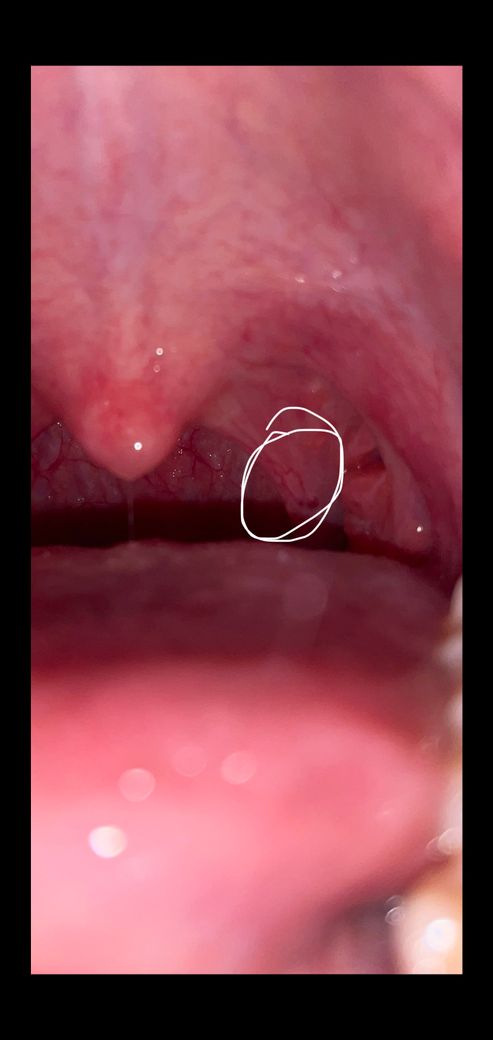

목젖뒤에 계속 염증이 생기는데 어느 병원으로 가봐야할까요?

계속 이물감이 있고, 사진에 동그랗게 친 염증 같은게 2주 넘게 지속되는거 같아서 병원에 가보려는데 치과로 가야하나요 이비인후과로 가야하나요?

인두부의 이상에 대한 진료를 원하시는 상황이므로 치과는 부적절하고, 이비인후과를 방문하시는 것이 가장 정확합니다.

사진으로볼때는 염증이 심해보이지는않습니다. 그냥 지켜보셔도되고 걱정된다면 근처 이비인후과 진료를 추천해드립니다